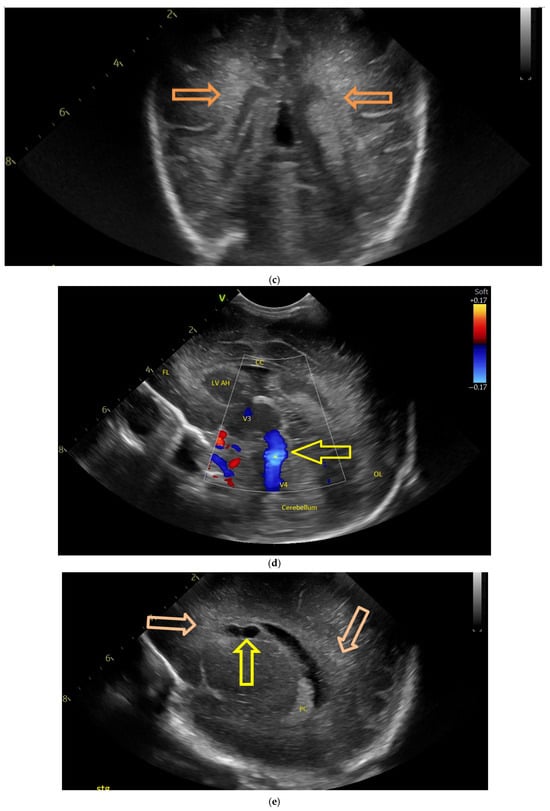

The first CUS was performed 24 h after birth and showed dilation of the third and fourth lateral ventricles, enlargement of the Sylvius aqueduct, and the presence of an arachnoid cyst (Figure 3a–e).

Figure 3.

(a) Cranial ultrasound. Coronal view. Enlargement of the lateral ventricles with hyperechoic and third ventricle dilation. D1, D2—Levine index measurement. D3, D4—anterior horn width measurement. D5—third ventricle (personal image collection). (b) Cranial ultrasound. Sagittal view. Up—left ventricle. D1, D2—lateral ventricle measurements and thalamo-occipital horn width. Down—right ventricle. D1, D2—lateral ventricle measurements and thalamo-occipital horn width (personal image collection). (c) Cranial ultrasound. Sagittal view. Up—enlargement of the third and fourth ventricles. Measurements of the ventricles. Down—measurement of the resistive index (RI) performed on the anterior cerebral artery (ACA) using Doppler flow measurements. RI—0.74 (personal image collection). (d) Cranial ultrasound. Transtemporal view. Yellow arrow—enlargement of the Sylvian aqueduct (personal image collection). (e) Cranial ultrasound. Sagittal view. Yellow arrow—arachnoid cyst posterior to the third ventricle (personal image collection). (f) Cranial ultrasound. Coronal view. Lateral ventricles and third ventricle enlargement. D1, D2—Levine index measurement. D3, D6—right lateral ventricle measurement (anterior horn width). D4, D5—left lateral ventricle measurement (anterior horn width) (personal image collection). (g) Cranial ultrasound. Sagittal view. Left—left ventricle. D1—thalamo-occipital distance measurement. Right—right ventricle. D2—thalamo-occipital distance measurement (personal image collection). (h) Cranial ultrasound. Coronal view. Up—orange arrow—third ventricle. Red arrow—fourth ventricles. Yellow arrow—arachnoid cyst. Down—resistive index measured on the anterior cerebral artery. RI—0.79 (personal image collection). (i) Cranial ultrasound. Transversal view. Up—RI precompression value on the middle cerebral artery performed with Doppler examination. RI—68. Down—RI post-compression value on the middle cerebral artery performed with Doppler examination. RI—0.79 (personal image collection). (j) Cranial ultrasound. Up—coronal view. L1, L2—Levine index measurement of the lateral ventricles. Down—sagittal view. L1, L2—measurement of the thalamo-occipital distance (personal image collection). (k) Cranial ultrasound. Sagittal view. L1, L2—measurement of the third ventricle. L3, L4—measurement of the fourth ventricle. L5, L6—measurement of the arachnoid cyst (personal image collection). (l). Head circumference-for-age. “X” symbols represent the measurements performed from birth and follow-up examinations. Head circumference was still under the curve during follow-up examinations (personal image collection) [28].

The CUS examination performed at 48 h after birth showed increases in the diameters of all ventricles. The resistive index presented an increase as well. The bregmatic fontanelle started bulging. The dimensions of the Sylvian aqueduct were not modified (Figure 3f–h).

The CUS examinations performed at four days and seven days after birth showed stabilization regarding the values of the diameters. The pre- and post-compression values of the resistive index of the middle cerebral artery showed a delta-RI of 0.11 (pre—0.68, post—0.79, Figure 3i).

After discharge, at three weeks after birth (follow-up examination), the ventricle measurements showed wider ventricles and the arachnoid cyst was still present (Figure 3j,k).

The next follow-up examination performed a week later showed a delta-RI of 0.12 and an increase in the cranial perimeter (+ one cm since the last follow-up).

At 12 weeks of life (five week corrected age), ventricle dilations were still present. Neurological examinations showed axial and limb hypotonia. The general movement examination showed a poor repertoire with a General Movement Optimality Score (GMOS) of 19. At 18 weeks of life (11 week corrected age), the neurological exam revealed that the infant presented plagiocephaly and could keep eye contact, and during the traction-to-sit maneuver showed hypotonia of the neck muscles. In the prone position, the infant was unable to hold the head up. The passive tone assessment showed the “scarf sign”, with the elbow at the midline bilaterally and a popliteal angle of 90° on the right and 110° on the left. Deep tendon reflexes were present. The general movement (GM) assessment revealed absent fidgety movements, with a Motor Optimality Score (MOS) of 13.